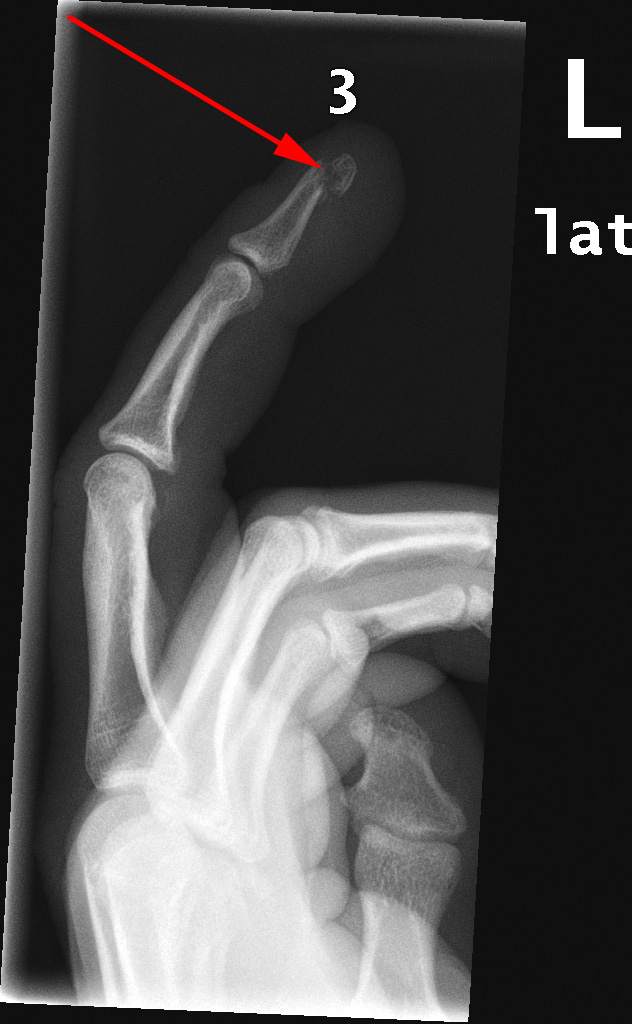

Røntgenundersøgelse af 3. venstre finger viser en fraktur i spidsen af den yderste knogle (rød pil).